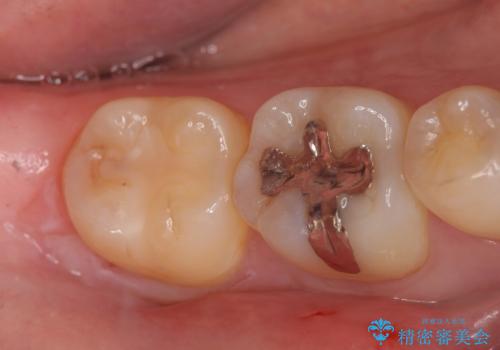

PGA(ゴールド)インレー 深い虫歯の治療